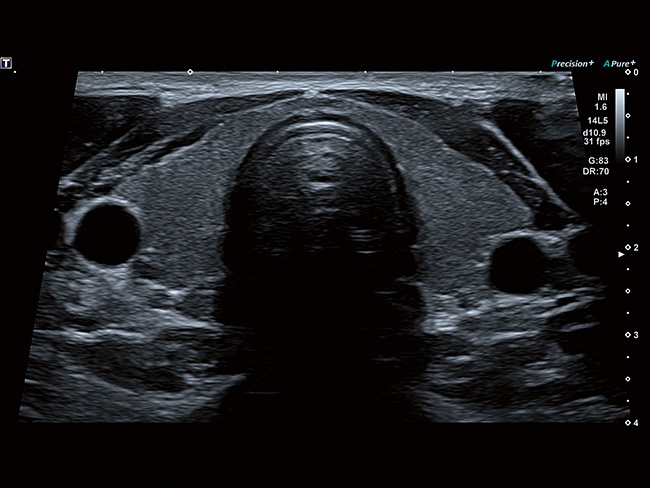

• MicroPure. Высокотехнологичное решение в области выявления микрокальцификатов – маркеров новообразований злокачественного типа. Маркеры идентифицируются путем изучения затененных изображений целевого участка. Микрокальцификаты отображаются в виде белых пятен.

• SMI. Опция, упрощающая визуализацию микроциркуляторного русла. С ее помощью обследуются сосуды с низкой интенсивностью кровотока, изучаются наиболее тонкие структуры. SMI упрощает диагностику новообразований, минимизирует вероятность ошибки.